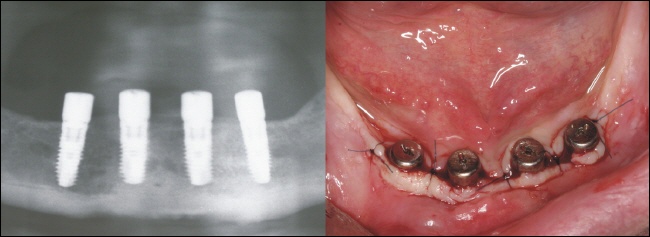

Einbringen der Implantate

||